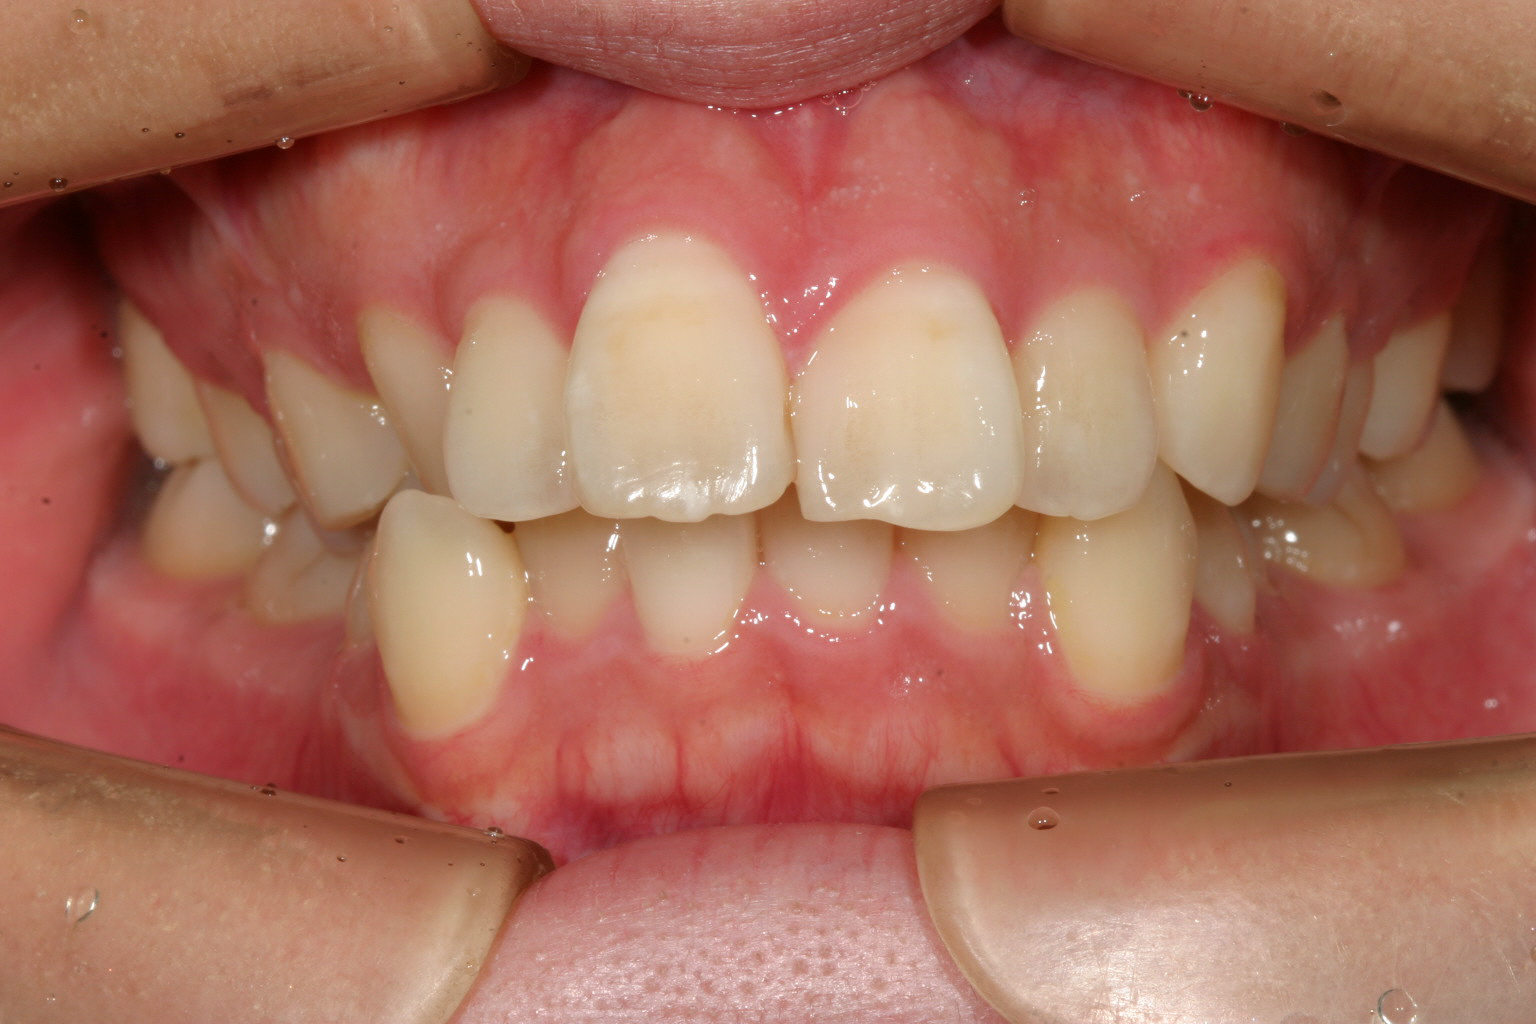

歯並びがガタガタ、下顎アーチが変形、出っ歯も気になる。

歯列がV字になっている為犬歯と犬歯の幅が狭く前歯が前に飛び出してます。

下顎はV字が特にひどく小臼歯あたりが狭くなっています。

かなりの出っ歯ですね~